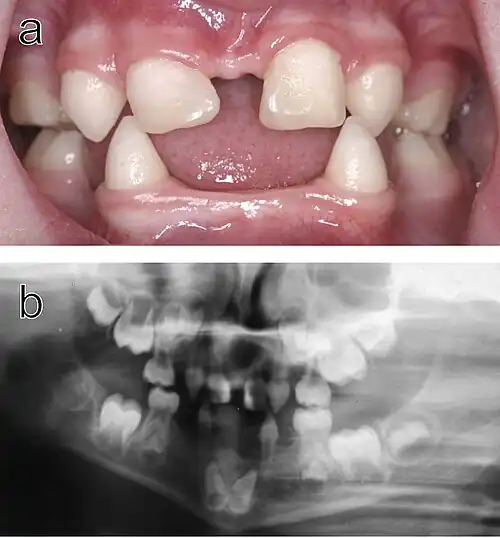

Ectodermal dysplasia is a rare but severe condition where the tissue groups (specifically teeth, skin, hair, nails and sweat glands) derived from the ectoderm undergo abnormal development. This is a diffuse term, as there are over 170 subtypes of ectodermal dysplasia. It has been accepted that the disease is caused by a mutation or a combination of mutations in certain genes. Research of the disease is ongoing, as only a fraction of the mutations involved with an ectodermal dysplasia subtype have been identified.[10]

.jpg)

Hypohidrotic ectodermal dysplasia (HED) is the most common subtype of the disease. Clinical cases of patients with this condition display a range of symptoms. The most relevant abnormality of HED is hypohidrosis, the inability to produce sufficient amounts of sweat, which is attributed to missing or dysfunctional sweat glands. This aspect represents a major handicap particularly in the summer, limits the patient's ability to participate in sports as well as his working capacity, and can be especially dangerous in warm climates where affected individuals are at risk of life-threatening hyperthermia. Facial malformations are also related to HED, such as pointed or absent teeth, wrinkled skin around the eyes, a misshaped nose along with scarce and thin hair. Skin problems like eczema are also observed in a number of cases.[11] Most patients carry variants of the X-chromosomal EDA gene.[12] This disease typically affects males more severely because they have only one X chromosome, while in females the second, usually unaffected X chromosome may be sufficient to prevent most symptoms.